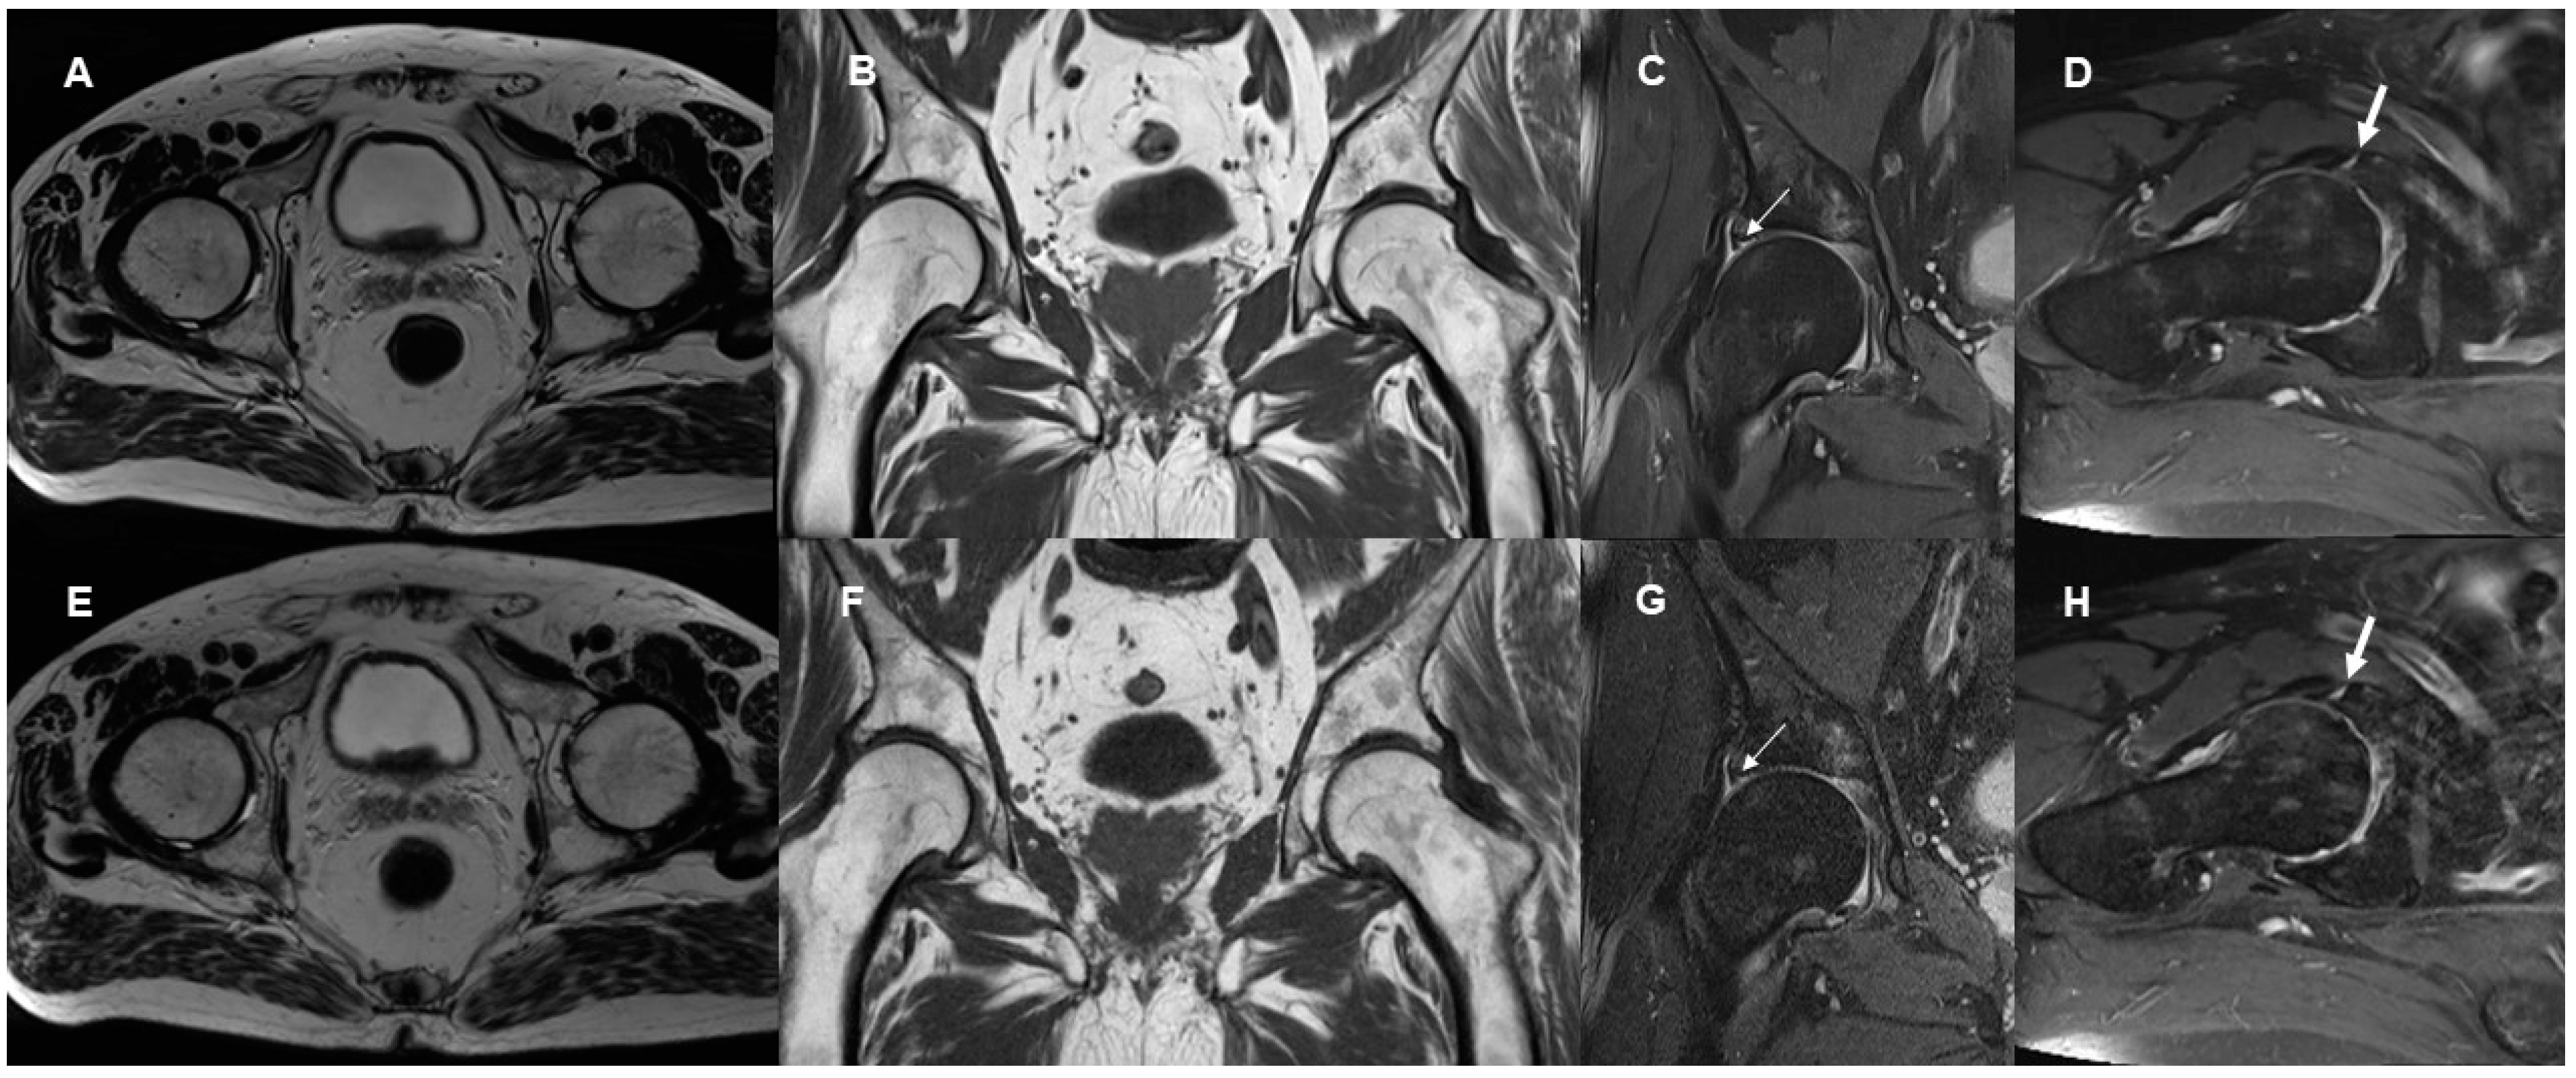

3.2. Delineation of Anatomic Structures and Internal Derangement